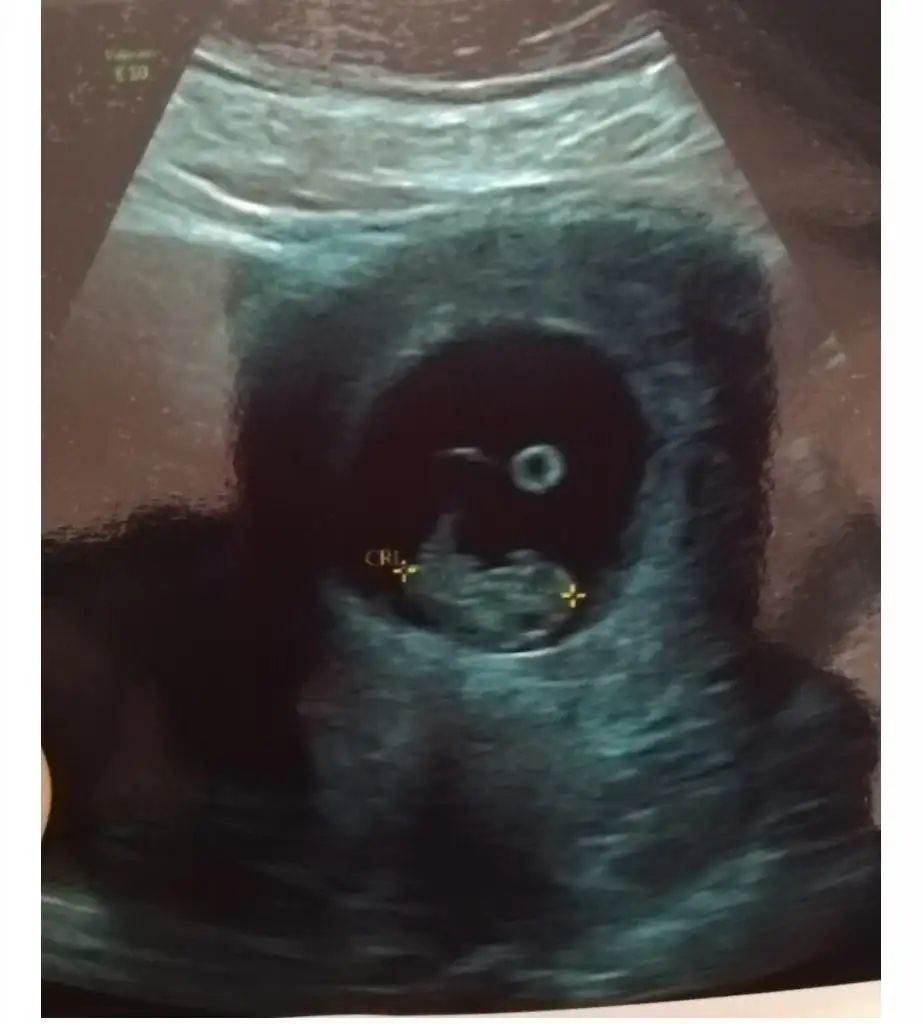

Bu var bideKız gibi sanki emin olamadım başka USG varsa paylaşın

8+5 yazıyor uygun değil nub için

Kese için sanki büyük gibiEki Görüntüle 2721564 bir de bu var 7 hafta

Tebrik ediyorum ya ben yanlış yazmışım haftası büyük cidden 8 haftalık ciddenKese için sanki büyük gibi8-9 hafta sanki buna göre de kız gibi 6-7 hafta varmı ama en iyi nub 11 12 13 haftalar

Usgde 9+6 yazıyorama bu en sonki 11 haftalik olanmis gelinimize srdumatti